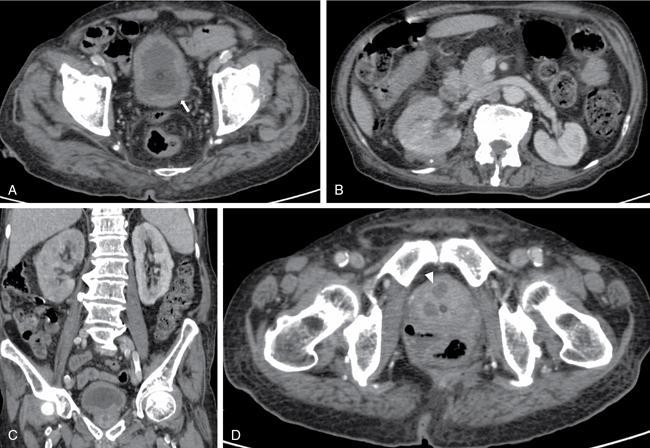

Acute cystitis (Fig. 10.13.3)

Image

Fig. 10.13.3 Acute cystitis, prostatic abscess and right sided pyelonephritis: Contrast enhanced CT Abdomen study of a 75-year-old male patient with burning micturition and fever spikes. Figure A demonstrates the irregular thickening of the urinary bladder (white arrow). Figure B and C show bulky right kidney with perinephric collection (white asterisk in B) suggestive of right pyelonephritis. Figure D shows peripherally enhancing collections within the prostate suggestive pf prostatic abscesses (white arrowhead).